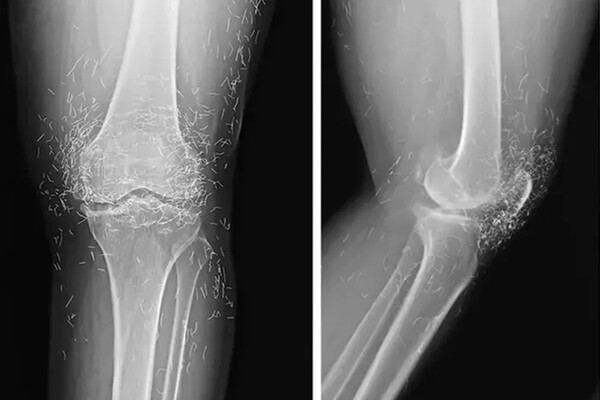

Рентген показал утолщение и деформацию костей, типичные признаки остеоартрита, а также сотни золотых фрагментов, внедренных в ткани вокруг коленного сустава. По словам специалистов, такая практика не имеет доказанной эффективности и несет серьезные риски.